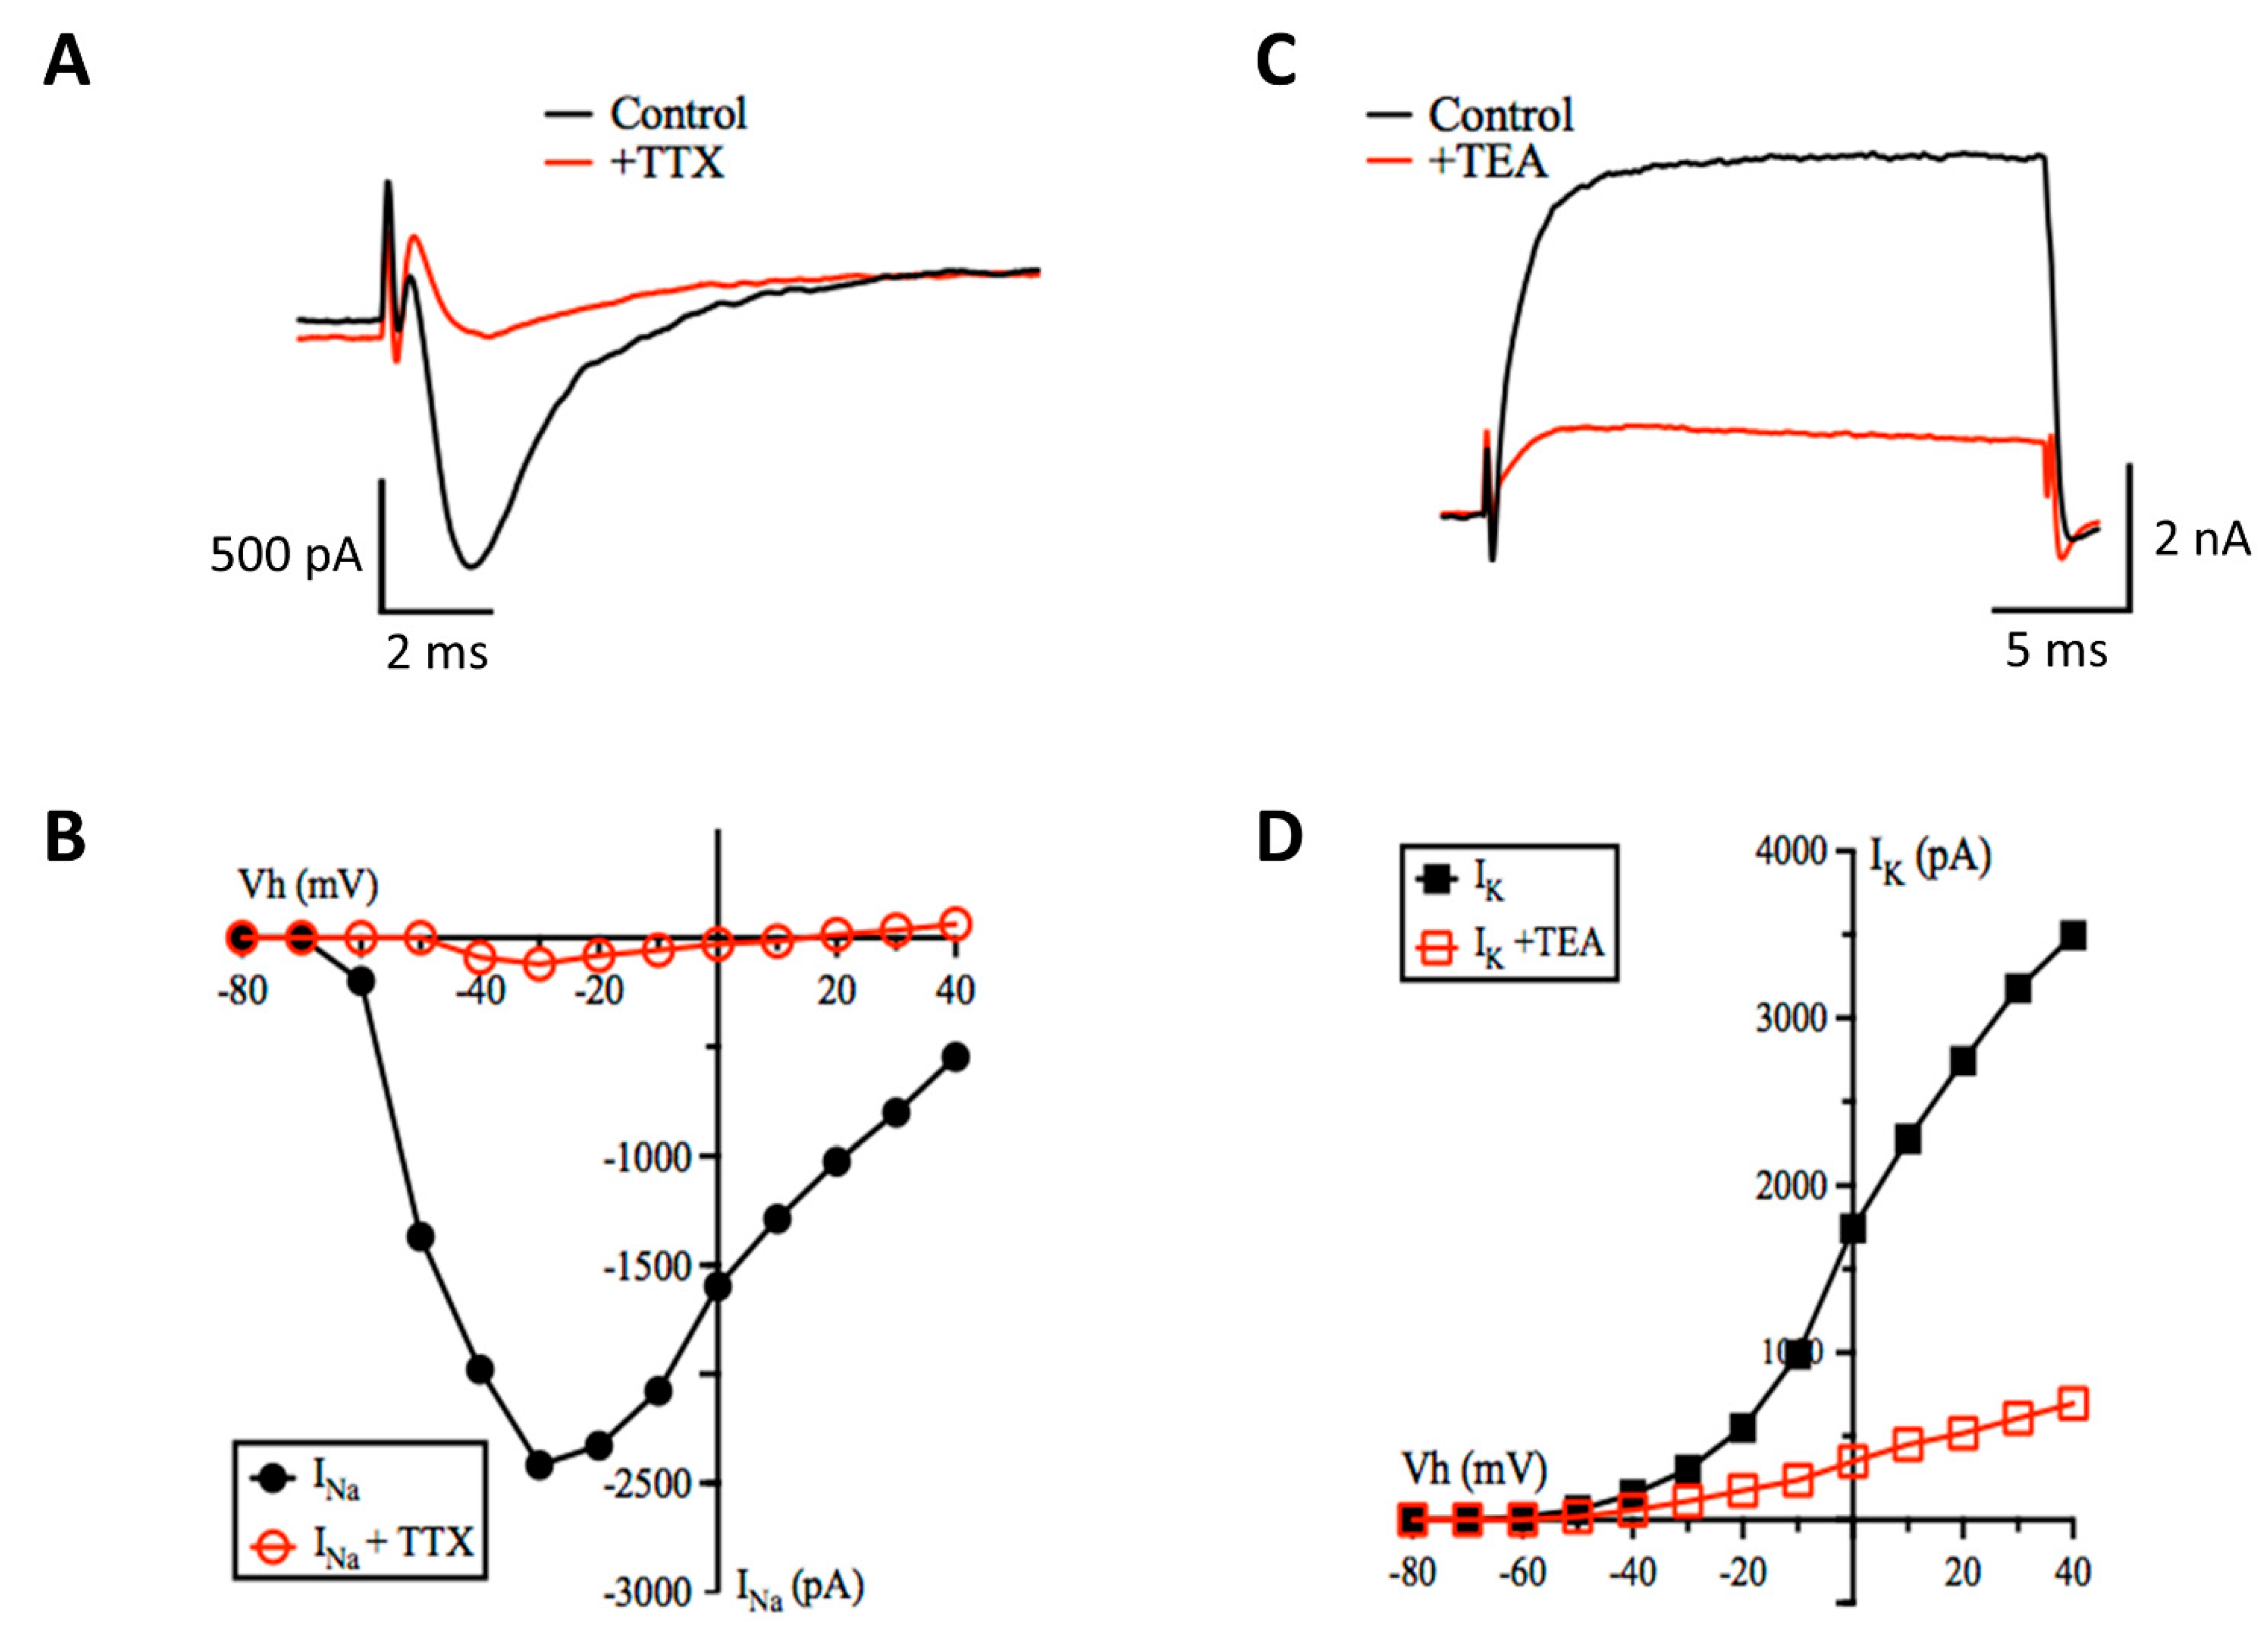

3.2. Patch-Clamp Electrophysiology